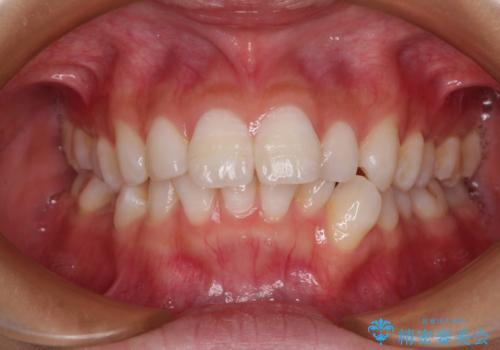

- 口を閉じたときに飛び出してしまう上顎前歯を気にして来院された患者様です。

下顎はデコボコが気になっていたため、上下左右第一小臼歯4本を抜去して、ワイヤー装置にて口元の突出感を改善するよう矯正治療を行うこととしました。